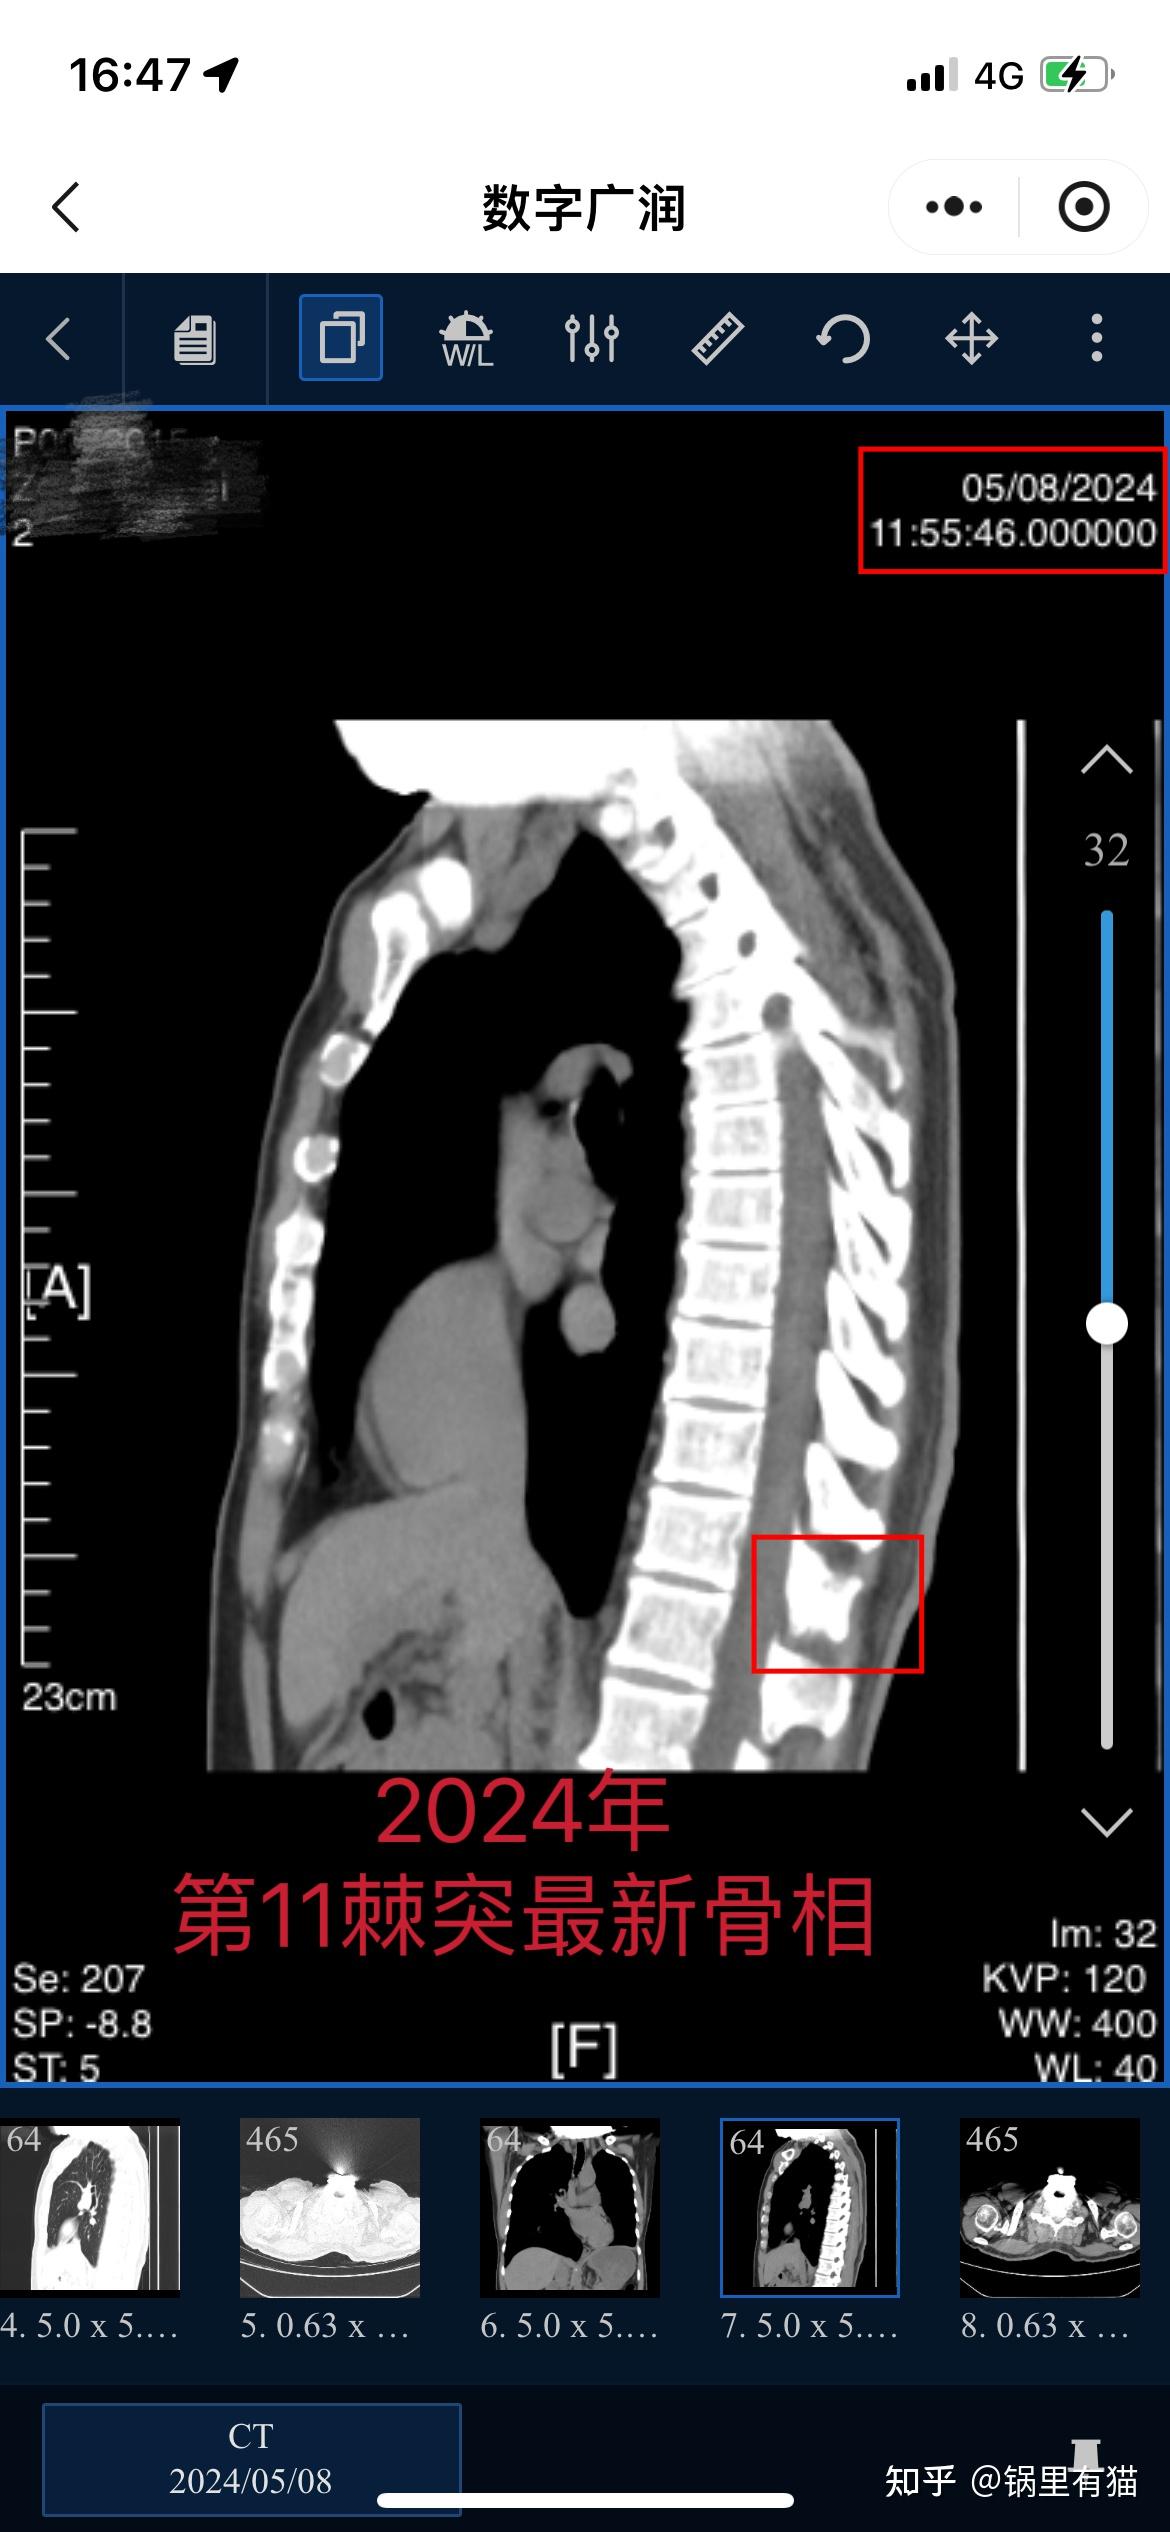

转移性骨肿瘤能治好吗

晚期或转移性骨癌治愈难度大若骨癌已进展至晚期或发生转移如扩散至肺肝等器官,治疗目标则转向控制癌症进展缓解症状及提高生活质量此时,传统治疗手术放疗化疗虽能延长生存期减轻疼痛并预防骨折,但完全治愈的可能性较低例如,转移性...